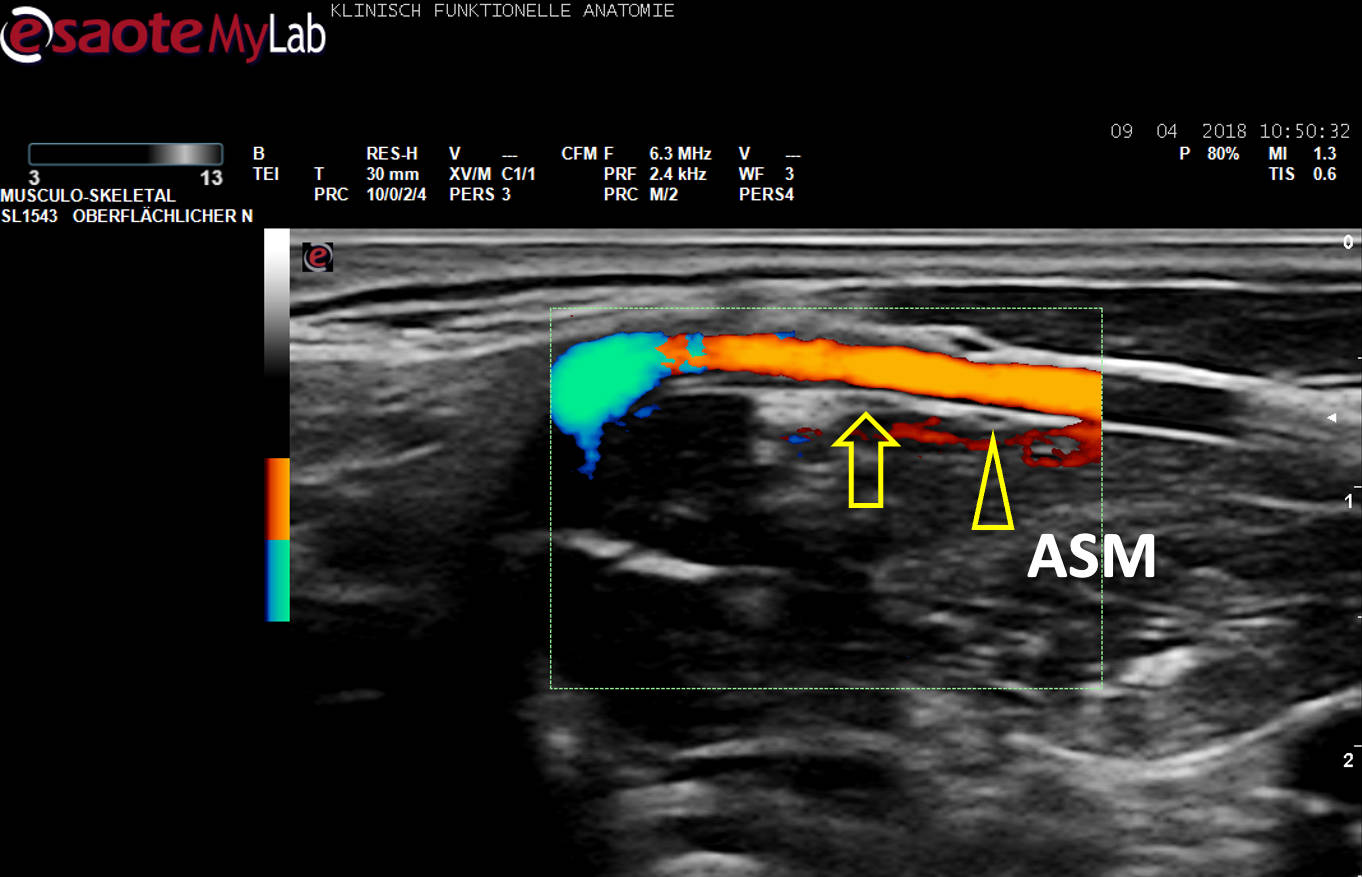

Beispiel der Detektion klinisch relevanter Varianten mit Hilfe des US am Lebenden.

US-Darstellung eines N. phrenicus accessorius (Pfeilkopf) aus C5 auf dem M. scalenus anterior (ASM), ein Gefäß (Farbe) unterkreuzend. Pfeil: N. phrenicus aus C4.